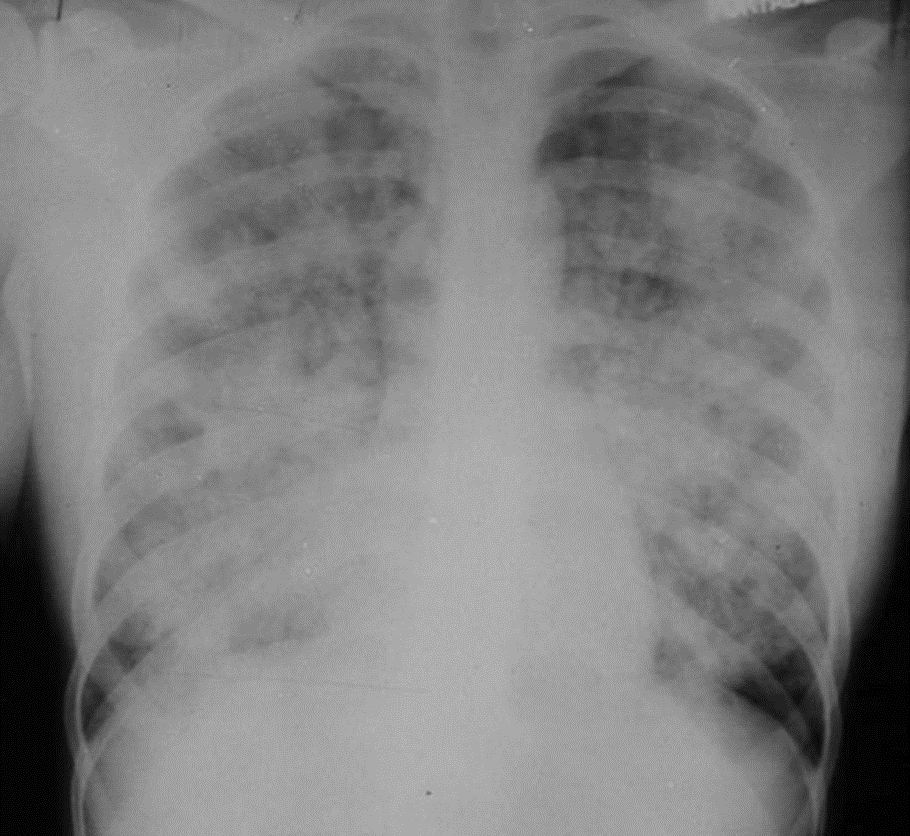

CXR Findings: Alveolar infiltrates (cotton balls)

ARDS

3. AP CXR shows bil infiltrates